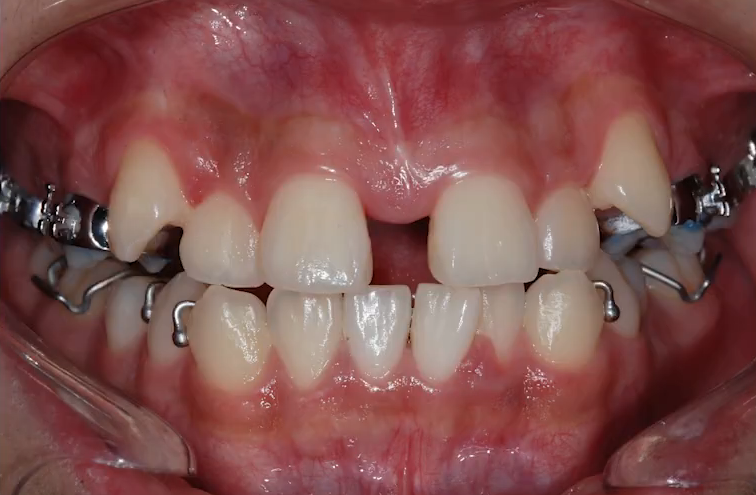

한편, 악궁을 확장하다 보면

앞니 사이가 틈이 벌어져 보이는 현상이 흔히 발생합니다.

처음엔 놀라실 수 있지만, 이는 치아가 제대로 움직이고 있다는 증거인데요.

후속 교정 과정에서 자연스럽게 다시 모아지게 되니 걱정하지 않으셔도 됩니다.

다만 이 단계에서 심미적인 스트레스를 느끼는 분들이 많아

저희는 이 시기를 미리 설명드리고, 진행 상황에 따라 부분 브라켓을 함께 사용해

불안감 없이 치료를 이어가실 수 있도록 도와드리고 있습니다.